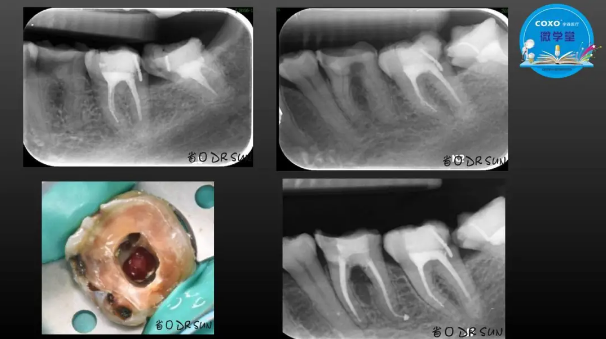

主任醫(yī)師,牙體牙髓副主任, 廣東省口腔醫(yī)院牙體牙髓科 主任醫(yī)師。2003年碩士研究生畢業(yè),研究方向為牙體牙髓病學,擅長于牙體牙髓病的診斷、齲齒、牙髓炎、根尖周病的治療以及前牙美容修復。